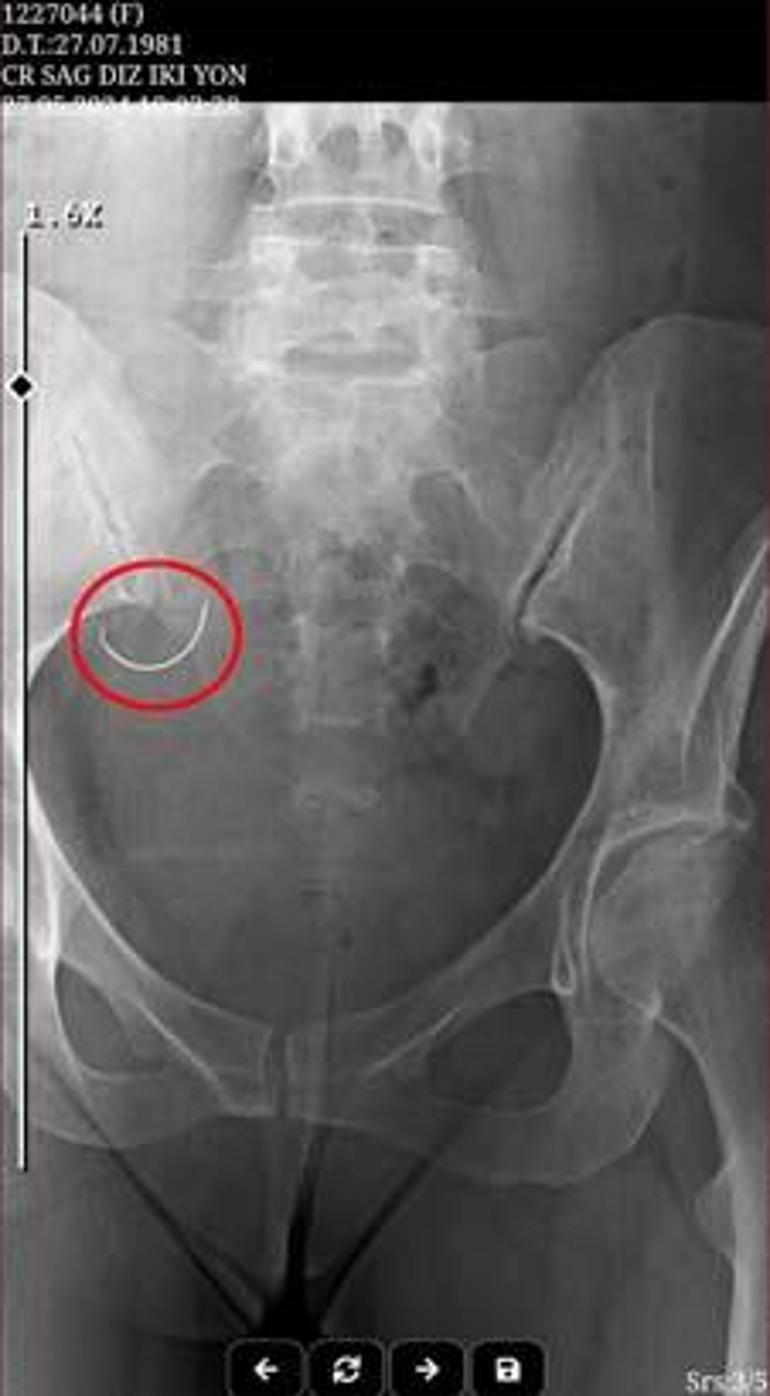

Operasyondan sonra Sabiha İ., şiddetli ağrılar yaşamaya başladı. Sabiha İ., ağrı nedeniyle tüp bebek tedavisi için gerekli ilaçları kullanamadı. Ü.İ., argümana nazaran bebek sahibi olamadıkları gerekçesiyle suçladığı eşine, 26 Mayıs 2024 tarihinde fizikî ve ruhsal şiddet uyguladı. Sabiha İ. olaydan 1 gün sonra isimli muayene için gittiği Kumluca Devlet Hastanesi’nde, karnında ameliyat iğnesi unutulduğunu, röntgen sineması sayesinde öğrendi. Hekimlerin sevk ettiği Antalya Eğitim ve Araştırma Hastanesi’nde yapılan ameliyat ile Sabiha İ.’nin karnındaki iğne alındı.